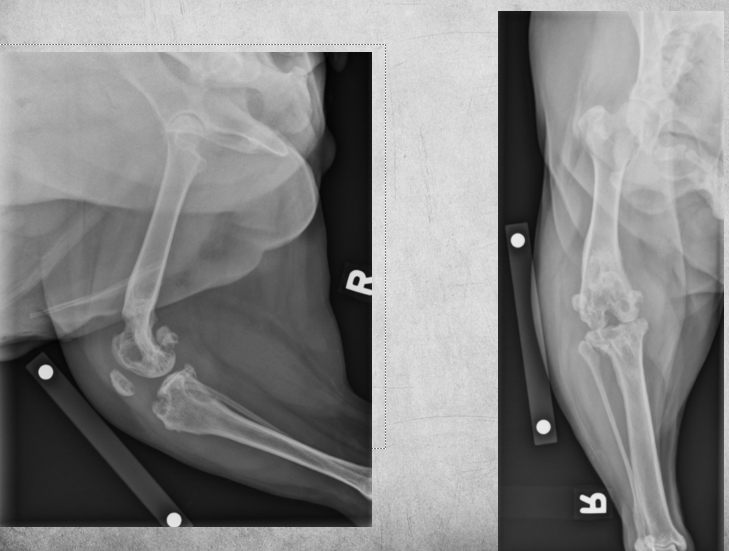

5 months old female Bernese Mountain dog

Played ball with other dogs the previous day

Weight-bearing lameness of left pelvic limb

Mild widening of the left tibial apophyseal physis and small fragment visible at distal portion ->

tibial crest avulsion fracture of growth plate in 5m large breed dog

analgesia and hope it heals okay